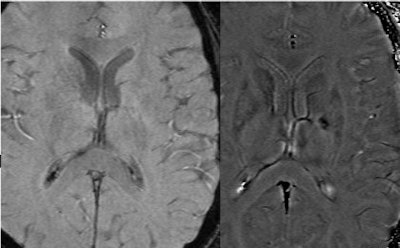

SWI in the brain offers amazing contrast on 1.5-tesla imaging and even better results at higher field strength magnets (3 tesla to 7 tesla). Recent collaborations with Dr. Yulin Ge at New York University in New York City using a 7-tesla system have revealed beautiful differentiation of gray and white matter, as well as the ability to differentiate venules from tissue with SWI.

| With high-field imaging, SWI gets faster because of shorter echo times and better because of increased signal-to-noise ratio. Here are some examples of 7-tesla imaging of the medullary veins, the gray matter and arcuate fibers surrounding the gray matter, pial veins, and venules branching from these veins. The pial veins are on the order of 0.5 to 1 mm, and the venules from 50 to 100 microns. Image courtesy of Dr. Yulin Ge, New York University in New York City, and E. Mark Haacke, Ph.D.; Sam Barnes; and Yingbiao Xu, Wayne State University, Detroit. |